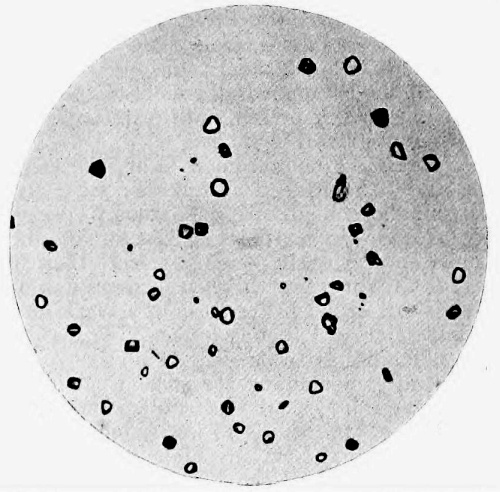

8. Measurement of Blood Corpuscles (human) 97

9. Measurement of Blood Corpuscles (sheep) 97

10. Photo-micrograph of Red Blood Corpuscles from Domestic Fowl 99

11. Photo-micrograph of Blood Corpuscles of Fish 99

12. Photo-micrograph of Blood Corpuscles from a Dried Stain of the Blood of a Cod-fish 100

13. Photo-micrograph of a Frog‘s Blood showing oval nucleated Red Corpuscles 101

14. Photo-micrograph of Crystals of Hæmin 102